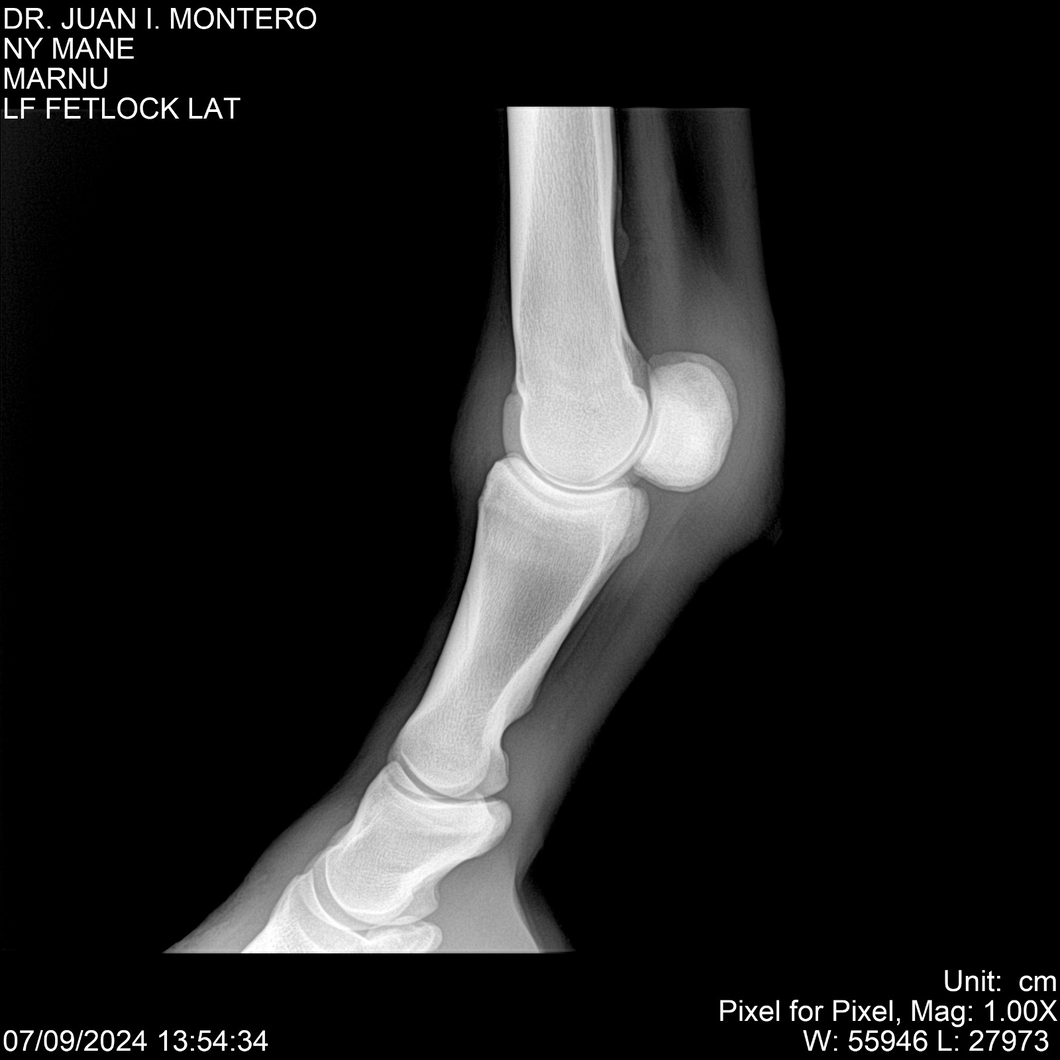

LOTE 20, NY MANE Lote Anterior Volver al remate Lote Siguiente Ficha Contacto Montevideo - Ficha del Lote Identificador: #282520 Categoría: Yeguarizos 76 Visualizaciones ClicData Contacto Empresa: Abelenda N. R., Walter Hugo Nombre*: Teléfono* : E-mail* : Mensaje Enviar Registrese gratis Este contenido Exclusivo está disponible sólo para usuarios registrados Ingresar